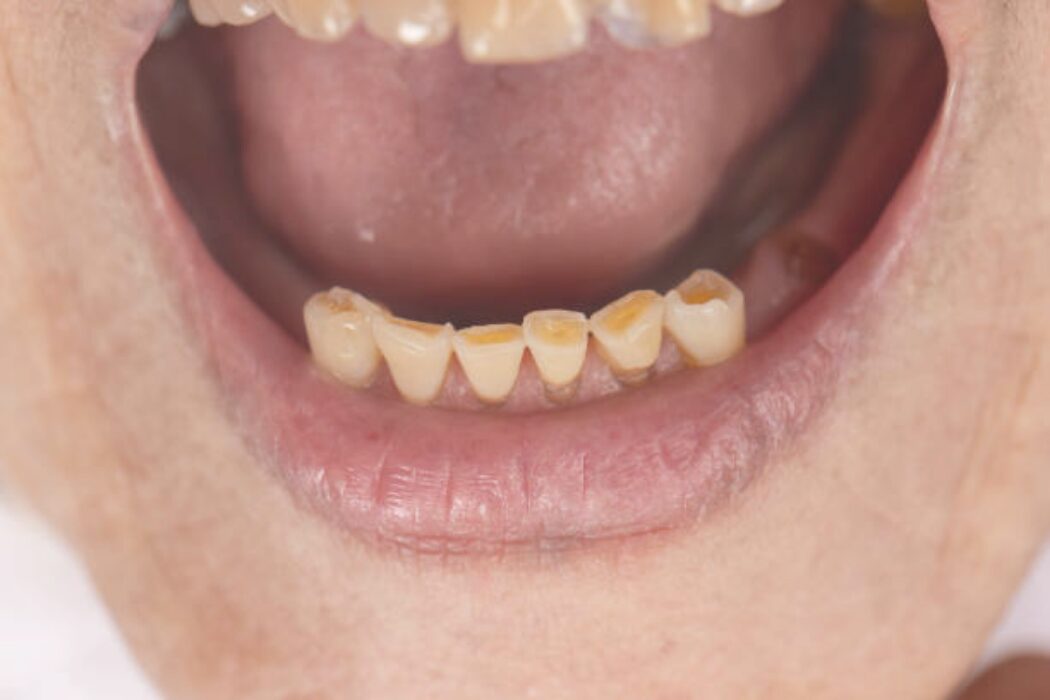

El bruxismo es una de las principales causas del desgaste dental. Detectarlo a tiempo permite evitar sensibilidad, fracturas y pérdida de estructura dental.

El desgaste dental no siempre está relacionado con la edad. Puede provocar sensibilidad, fracturas y cambios en la sonrisa. Detectarlo a tiempo permite proteger los dientes y evitar tratamientos más complejos.